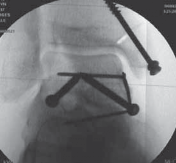

Comminuted fractures should be buttressed by mini-screw and plate fixation to resist displacement against axial loads to the process ( TECH FIG 5C,D).

A B C

TECH FIG 5 • Lateral process fracture of talus. A. Preoperative CT image. B. Intraoperative view of fracture. C. Intraoperative view of fixation. D D. Postoperative image. #### EXTERNAL FIXATION